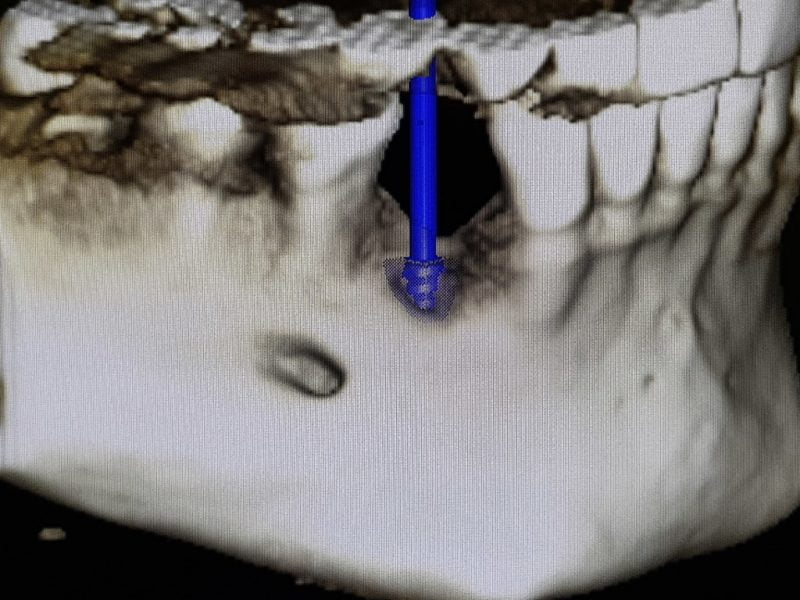

This case is presenting immediate implant placement in lower jaw in premolar region with lack of bone height and width. Patient had complicated extraction of root 44 which lead to greater bone loss. Implant placement was carefully planned with the help of 3D CBCT scan. Since there was lack of bone height towards mental canal, we planned to leave part of the implant not covered by bone and above crest line. Missing bone was augmented with the help of artificial bone regeneration material in combination with platelet rich fibrin creating “sticky bone”. Implant used in this case was 3P by B&B dental, and later we placed screw-retained metal-ceramic crown.